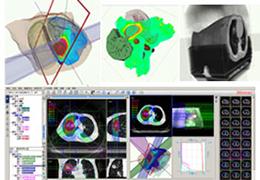

Data Analysis

Data Analysis

Data analysis includes preprocessing, correlation analysis, determination of Talairach coordinates, volume rendering, surface rendering and cortex flattening.

Preprocessing includes motion correction, Gaussian spatial and temporal data smoothing, linear trend removal and filtering in the frequency domain.

Statistical Analysis

BrainVoyager performs a wide range of statistical analyses including; parametrical mapping, contribution maps, Independent Component Analysis (ICA), Region-of-interest analysis and Event-related fMRI analysis. specifications.

Visualization Tools

Parametric and non-parametric statistical maps may be superimposed both on the original functional scans as well as onto T1-weighted 2D or 3D anatomical reference scans. Time courses of selected regions-of-interest (ROIs) are available both in 2D and 3D representations. Statistical maps may be computed either in the 2D or 3D representation since structural as well as functional 4D data (space x time) are transformed into Talairach space. This allows you to compare activated brain regions across different experiments and across different subjects

Segmentation

Segmentation of tissue (e.g., isolating the brain, differentiating gray and white matter) is performed using region-growing methods, filter operations as well as the application of 3D templates. Using the mouse it is very easy to explore a 3D volume with superimposed pseudocolor-coded statistical maps in a four-window representation showing a sagittal, coronal, transversal and oblique section. Based on a (segmented) 3D data set a three-dimensional reconstruction of the subjects' head and brain can be calculated and displayed from any specified viewpoint using volume or surface rendering.

Volume Rendering

Volume rendering is performed with a very fast ray casting algorithm; lightning calculations are based on Phong-shading. Surface rendering of reconstructed surfaces is performed using OpenGL. Using texture mapping, a reconstructed surface (e.g., head or brain) may be sliced in real time, showing both surface and volume data at the same time. Initial polygon meshes serve as the basis for surface finding, cortex inflation and cortex flattening computations.

Surface Reconstruction

The surface reconstruction procedure starts with a sphere (recursively tesselated icosahedron) or a rectangle, which slowly wraps around a (segmented) volume data set. In order to avoid topological defects and to let the surface smoothly grow into deep sulci, a dynamic mesh algorithm was developed which automatically invents new polygons on the fly at places where they are needed. A reconstructed cortical surface may be inflated, cut interactively and slowly unfolded minimizing areal distortions. Statistical 3D maps may be superimposed on reconstructed, inflated or flattened cortex. Signal time courses may be invoked by simply pointing to any region of a visualized surface.